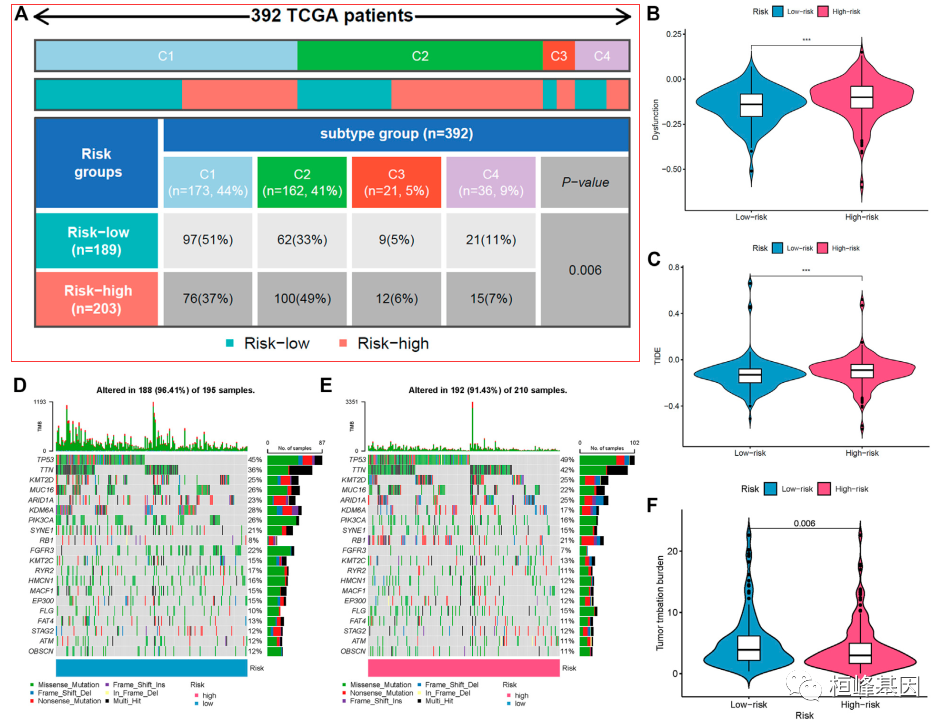

我们也可以将此类的图形放在自己的文章中,比如参考文献中的A图就是利用矩形树状图的原理分析了整个 TCGA-BC 数据集的免疫与高低风险组之间的比例关系,没有在文章中找到类似的数据,所以我们并没有复现,但是文章中的描述我们参考一下,后期可以考虑添加到自己的文章中。

The mechanism of the five lncRNAs may be related to immune response. Furthermore, type C1 (wound healing) immunization is the main immunization mode in the low-risk group, whereas type C2 [interferon-γ (IFN-γ) dominant] immunization accounts for a high proportion in the high-risk group (Figure 8A). The proportion of type C3 (inflammatory) and type C4 (lymphocyte depleted) immunization was low in the two groups. The difference of molecular typing of immune subtypes between the two risk groups was statistically significant.